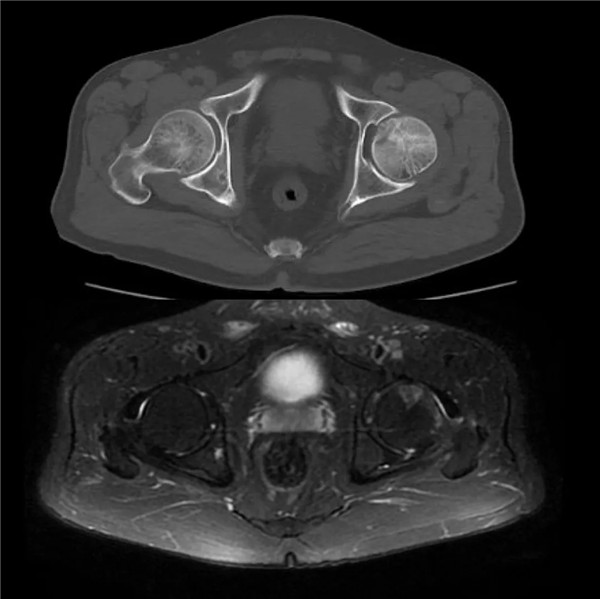

(CT和磁共振顯示:髖關(guān)節(jié)撞擊征合并股骨頭壞死)